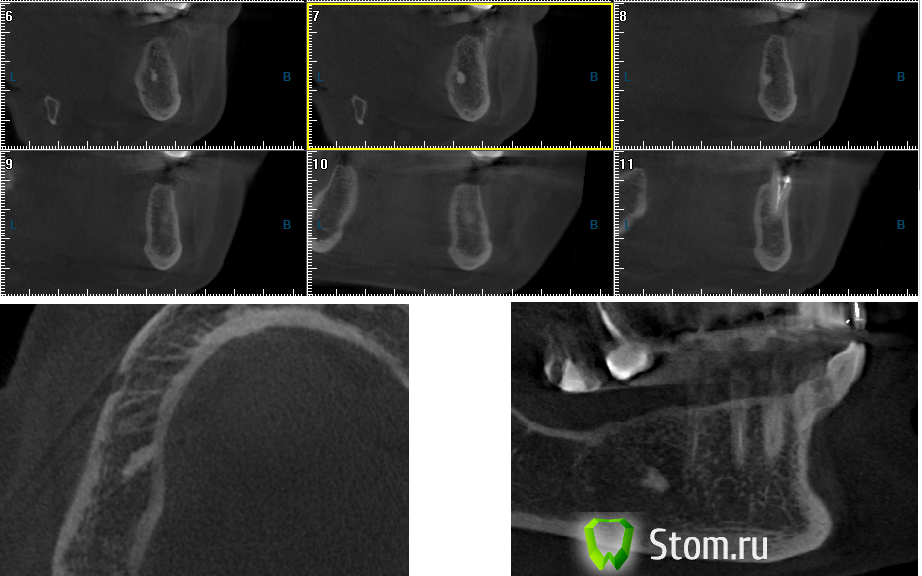

OlegKiev Опубликовано 31 марта, 2012 Поделиться Опубликовано 31 марта, 2012 Здравствуйте уважаемые коллеги, поскажите что это может быть: -остатки пломбировочной массы?-остеома?-другой вариант Зубы были удалены более 15 лет назад. Симптомов нет. Можно ли допустить контакт импланта с образованием? Заранее спасибо! Ссылка на комментарий

Petr_Off Опубликовано 1 апреля, 2012 Поделиться Опубликовано 1 апреля, 2012 (изменено) Мне кажется, что это участок уплотнения в кости. Для пломбировочного не очень характерная локализация по слайду №8 - слишком близко к язычной кортикальной - верхушка корня все же ближе к вестибулярной кости. Однажды коллеги (у пациентки были боли неопределенного характера и локализации, а на Rg нашли похожую картинку) "залезли" в кость и ничего не нашли - обычная такая кость . Я бы не обращал внимания на это. Изменено 1 апреля, 2012 пользователем Petr_Off Ссылка на комментарий

Jedi Опубликовано 1 апреля, 2012 Поделиться Опубликовано 1 апреля, 2012 Можно установить имплант 10мм без контакта с этим образованием, возможно это остеома, но специально удалять ее до или во время имплантации не надо, это мое личное мнение Ссылка на комментарий